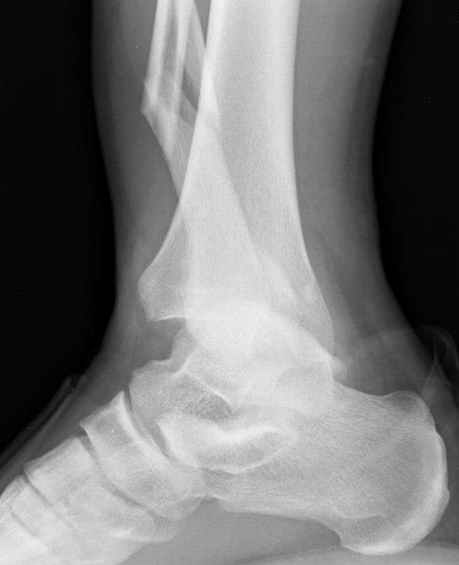

С мнением «провести позиционный межберцовый винт чуть ниже пластинки в положениий тыльного сгибания стопы» согласен, но я бы нагрузку начал через три недели и удаление шурупа можно провести через 6-8 недель.

Для облегчения удаления сломанных шурупов (случается часто) рекомендую фиксацию двумя 3.5мм кортикальными шурупами на 3 мм длиннее, тот же сломанный шуруп легко удаляется с медиальной стороны.

Здесь похожий случай трехнедельной давности, перелом почти сросся и была укорочена малоберцовая, на операции длину малоберцовой смогли восстановить только после того, когда проксимальнее пластины ввели шуруп и использовали его как толкатель, с помощбю дистракционого инструмента (lamina spreader).

Меньше всего волнует положение медиальной лодыжки - в любое время можно провести остео или реостеосинтез, при несращении можно просто резецировать без ущерба для движений в голеностопе. Здесь обошлись фиксацией одним 4 мм канюлированным шурупом.